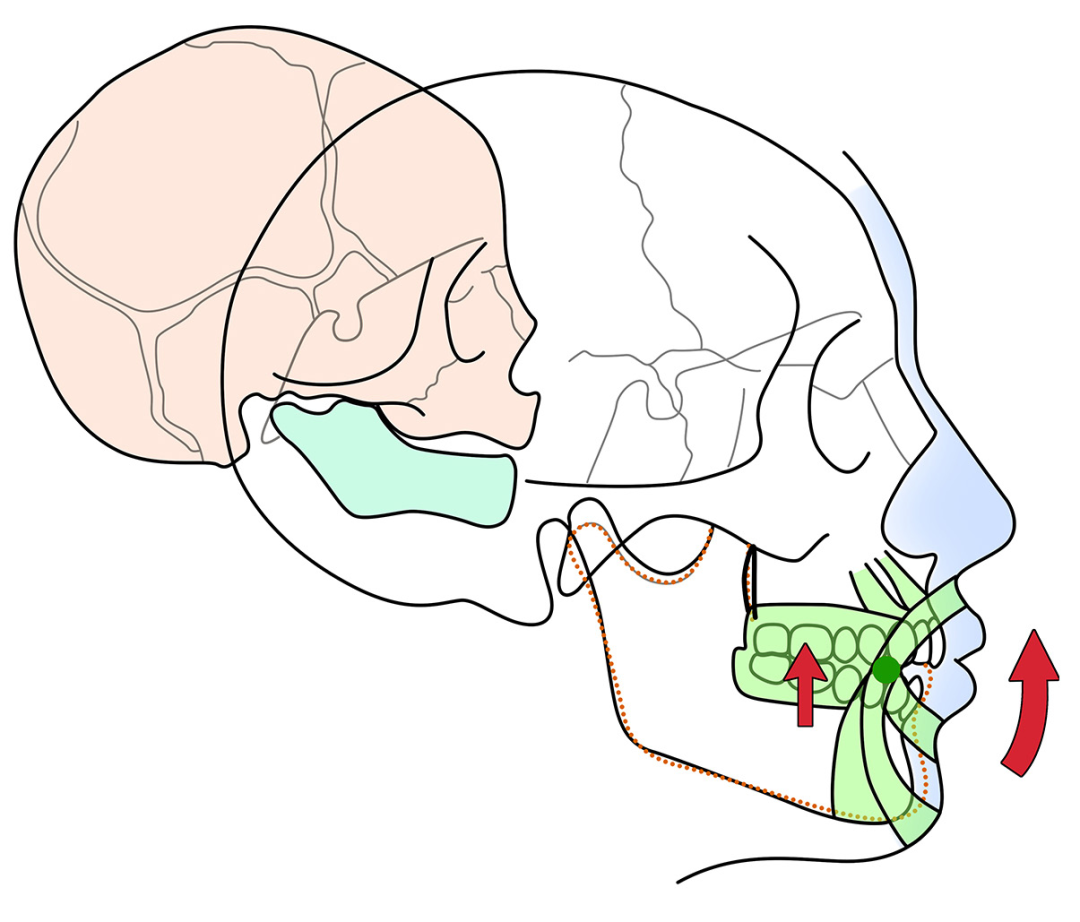

简单地说,Clarks医生认为上下牙齿的咬合斜面,会传导咬合力到牙槽骨,不同的咬合斜面传导到牙槽骨的力的方向不一样。

也就是说I类的咬合斜面,咬合力传导到牙槽骨是I类的刺激牙槽骨改建的力量。II 类的咬合斜面,咬合力传导到牙槽骨是II类的刺激牙槽骨改建的力量。

因此改变II类的咬合斜面,就可以改变刺激颌骨改建的II类力量。给II类的患者带上I类咬合关系的咬合板,在II类患者的口内模拟I类的咬合关系,引导下颌向前,促进下颌生长。

那么颌板把这个收缩的力量就传导到牙齿,就会对上下磨牙产生压入的力量,抑制后牙萌出,如此保存上下颌差异性生长产生的颌间间隙,颌间间隙能够促进下颌逆时针旋转,下颌颏部前移。